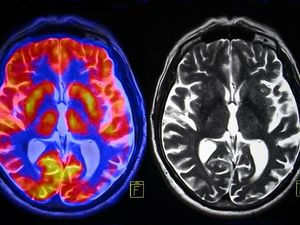

The device, developed by San Francisco-based start-up Openwater, can scan the brain and body with a resolution a billion times higher than an MRI (Magnetic Resonance Imaging) machine.

Using opto-electronics, the wearable could replace the functionality of a large MRI machine, enabling constant monitoring. This would aid treatment of cancer, cardiovascular diseases, neurodegenerative diseases, and could allow for communication using thought alone.

Tumours and artery clogs can be detected by scanning the surrounding blood flow. Openwater’s goal is to have the device follow the flow of oxygenated blood to different parts of the brain and “read” thoughts.

The research demonstrated that scientists could identify which video the student was watching based on oxygen flow in the brain. New technology aims to replicate this, but far more accurately.

Once developed, the wearable will have the ability to receive clear images based on blood-flow in the brain, which could allow a person to upload their thoughts directly to a computer.